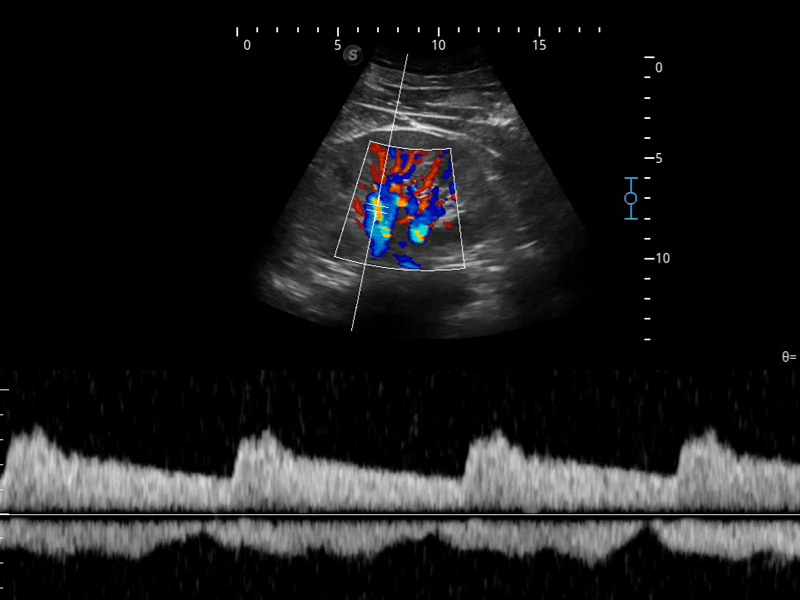

凭借开立医疗先进的成像技术和优异的探头技术提供的清晰的图像表现,您可以更自信地做出临床决策。